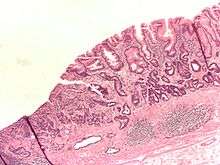

Intestinal metaplasia (top middle of image) of the gastric antrum and adenocarcinoma of the stomach (left/centre of image). H&E stain.

Intestinal metaplasia is the transformation (metaplasia) of epithelium (usually of the stomach or the esophagus) into a type of epithelium resembling that found in the intestine. In the esophagus, this is called Barret's esophagus. Chronic inflammation caused by H. pylori infection in the stomach and GERD in the esophagus are seen as the primary instigators of metaplasia and subsequent adenocarcinoma formation. Initially, the transformed epithelium resembles the small intestine lining; in the later stages it resembles the lining of the colon. It is characterized by the appearance of goblet cells and expression of intestinal cell markers such as the transcription factor, CDX2.